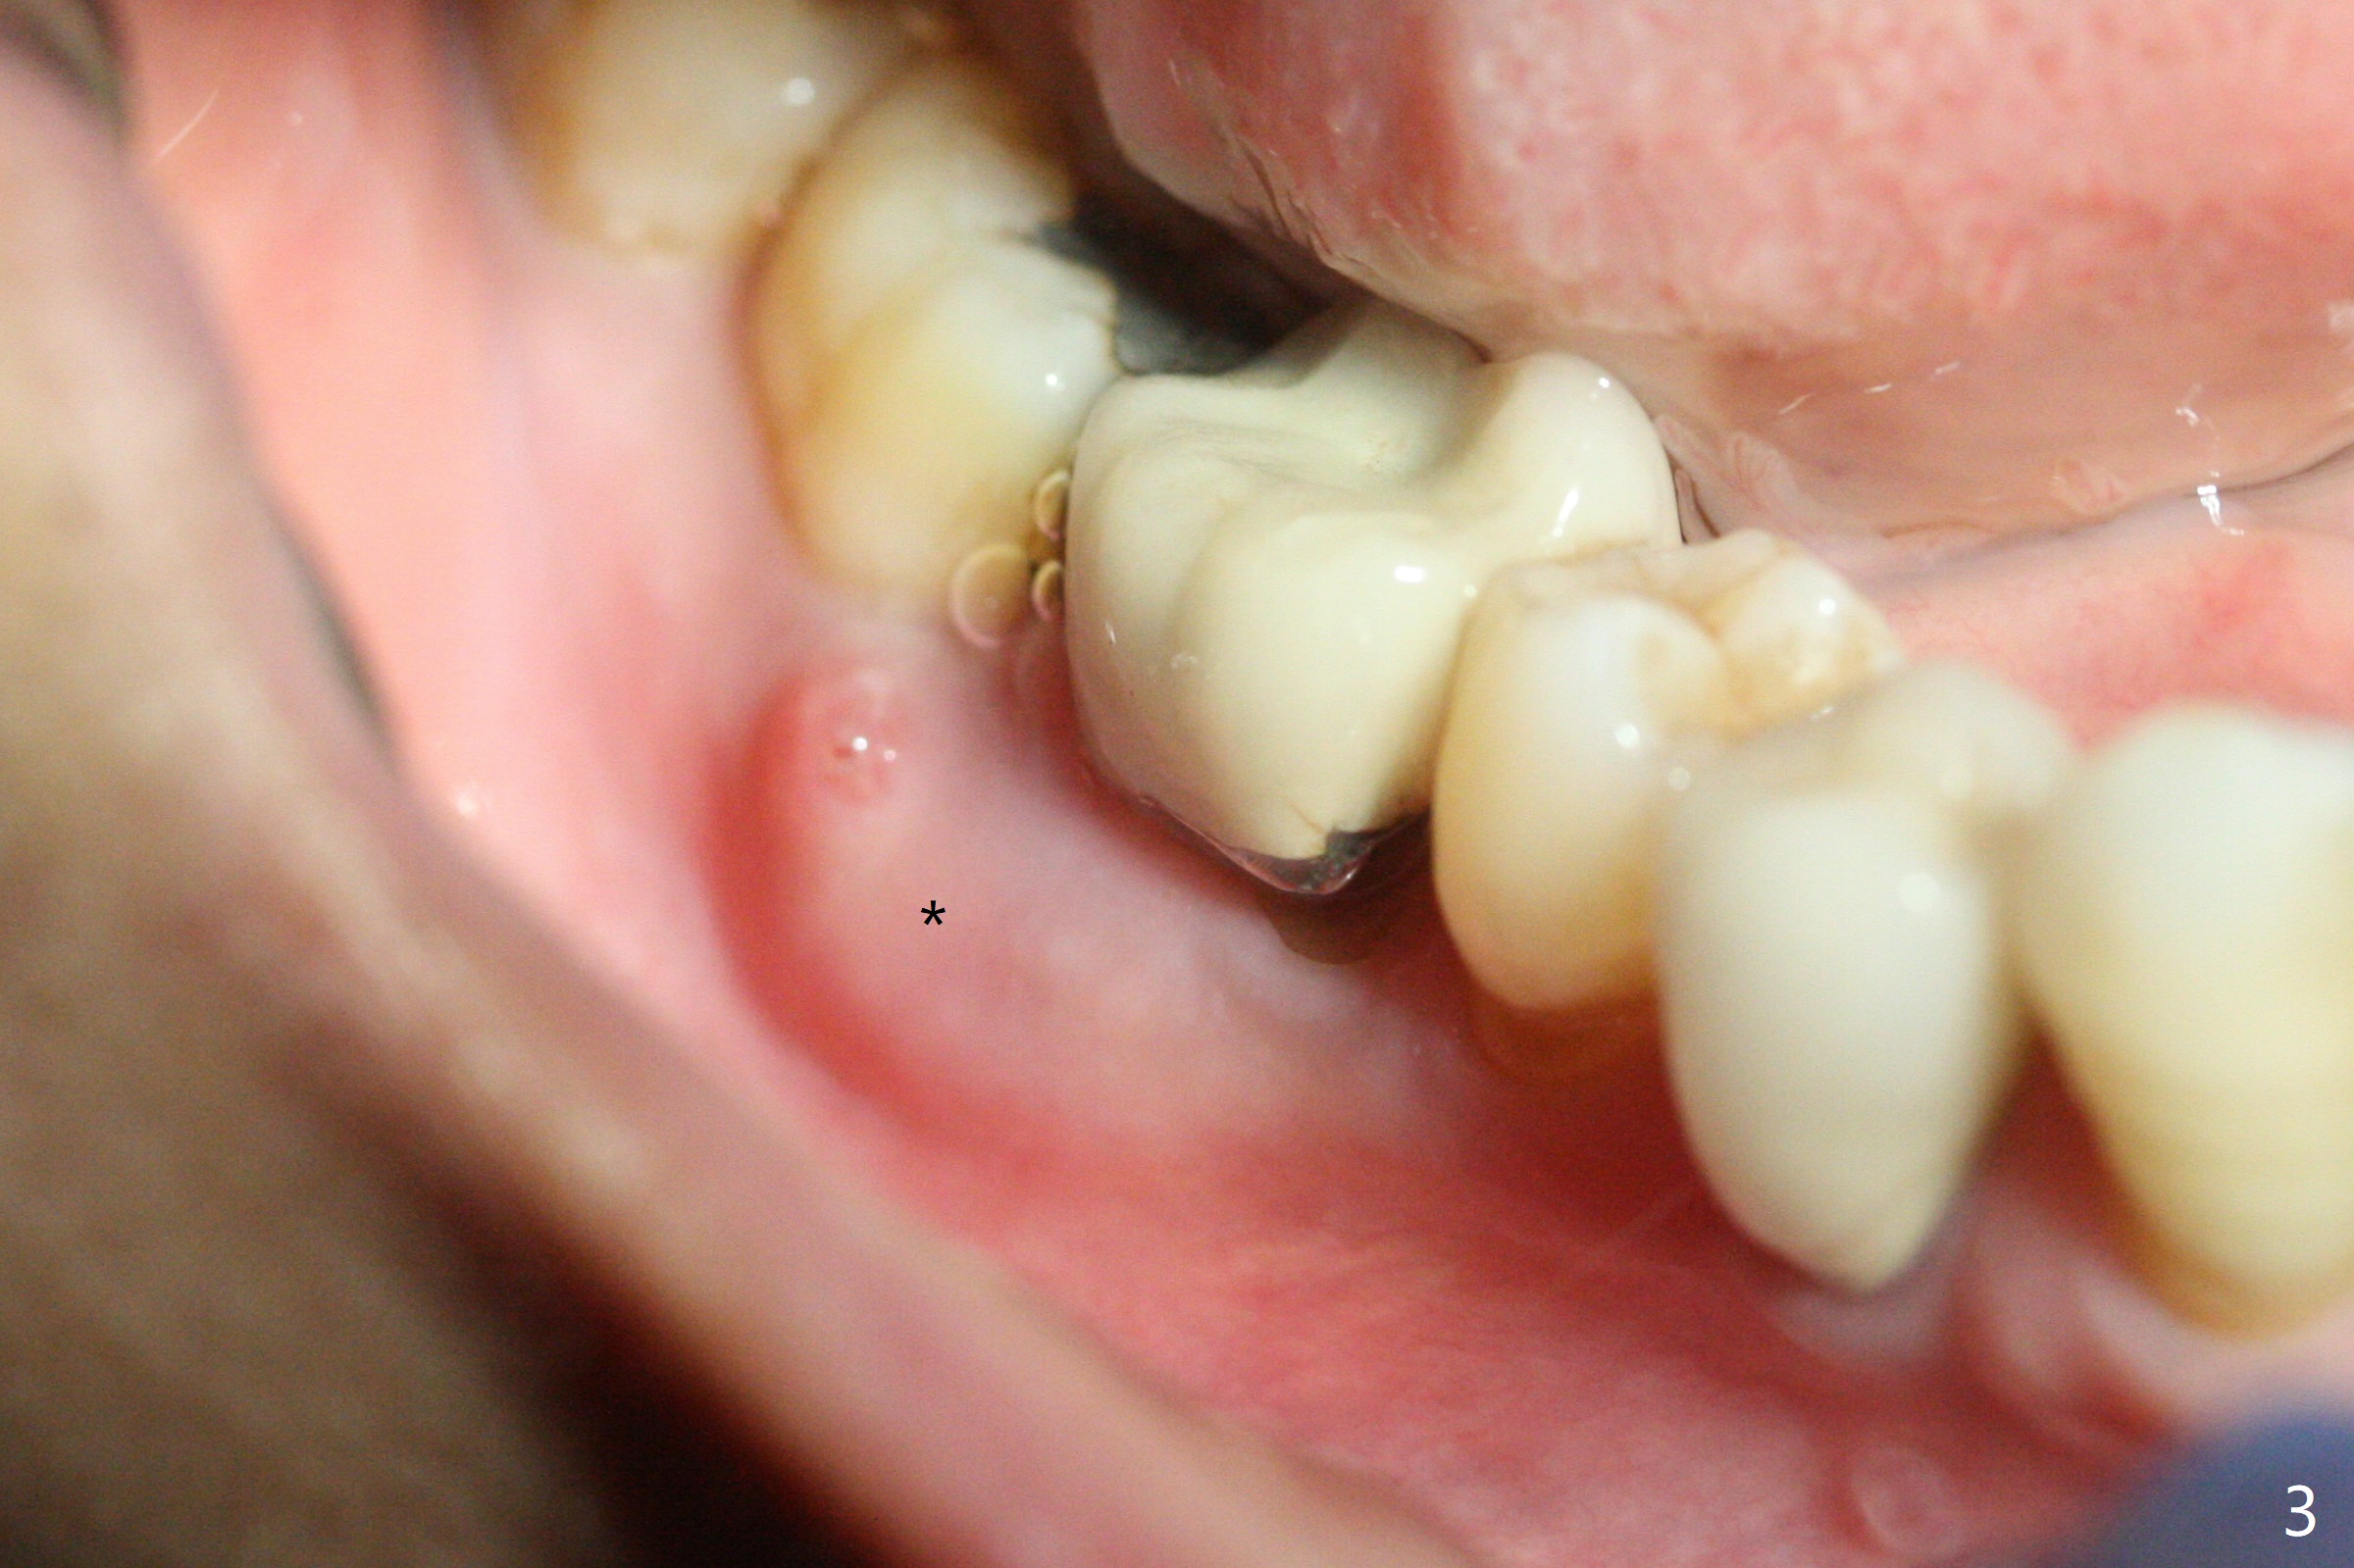

A 66-year-old woman loses a lot of bone at #30 in 4-5 months (Fig.1,2). There is severe buccal swelling, suggesting loss of the buccal plate and easy collapse of the gingiva after bone graft. In addition to an immediate provisional, periodontal dressing will be applied for support and seal. To prevent abutment screw loosening, guide will be used for implant placement in the most ideal trajectory (Fig.4). A tissue-level implant will provide with more security in prevention of screw loosening (Fig.5). If immediate implant is impossible, bone graft will be placed. Four months later, retake 5x5 cm CT for lab to determine the fitness of the guide.